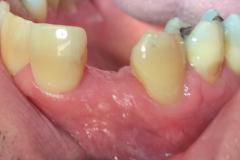

Immediate implant placement with simultaneous bone augmentation and connective tissue grafting. The case will be completed with crown lengthening, veneer replacement, and soft tissue optimisation to achieve ideal emergence profiles.